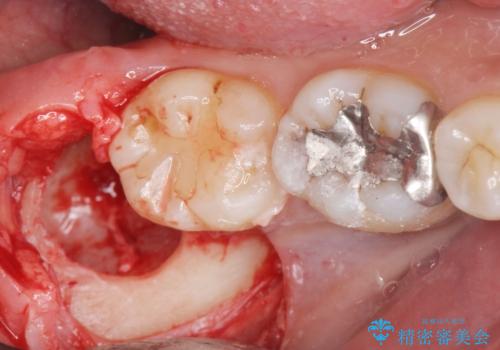

親知らず抜歯

- 親知らずの抜歯を希望された患者様です。

CTを撮り下顎の神経が近くない事を確認し抜歯を行いました。

親知らずの場所は磨きにくく、虫歯になるリスクが非常に高いです。

また親知らずの手前の歯の虫歯のリスクが高くなります。

なので虫歯になる前に抜歯をすることをお勧めします。